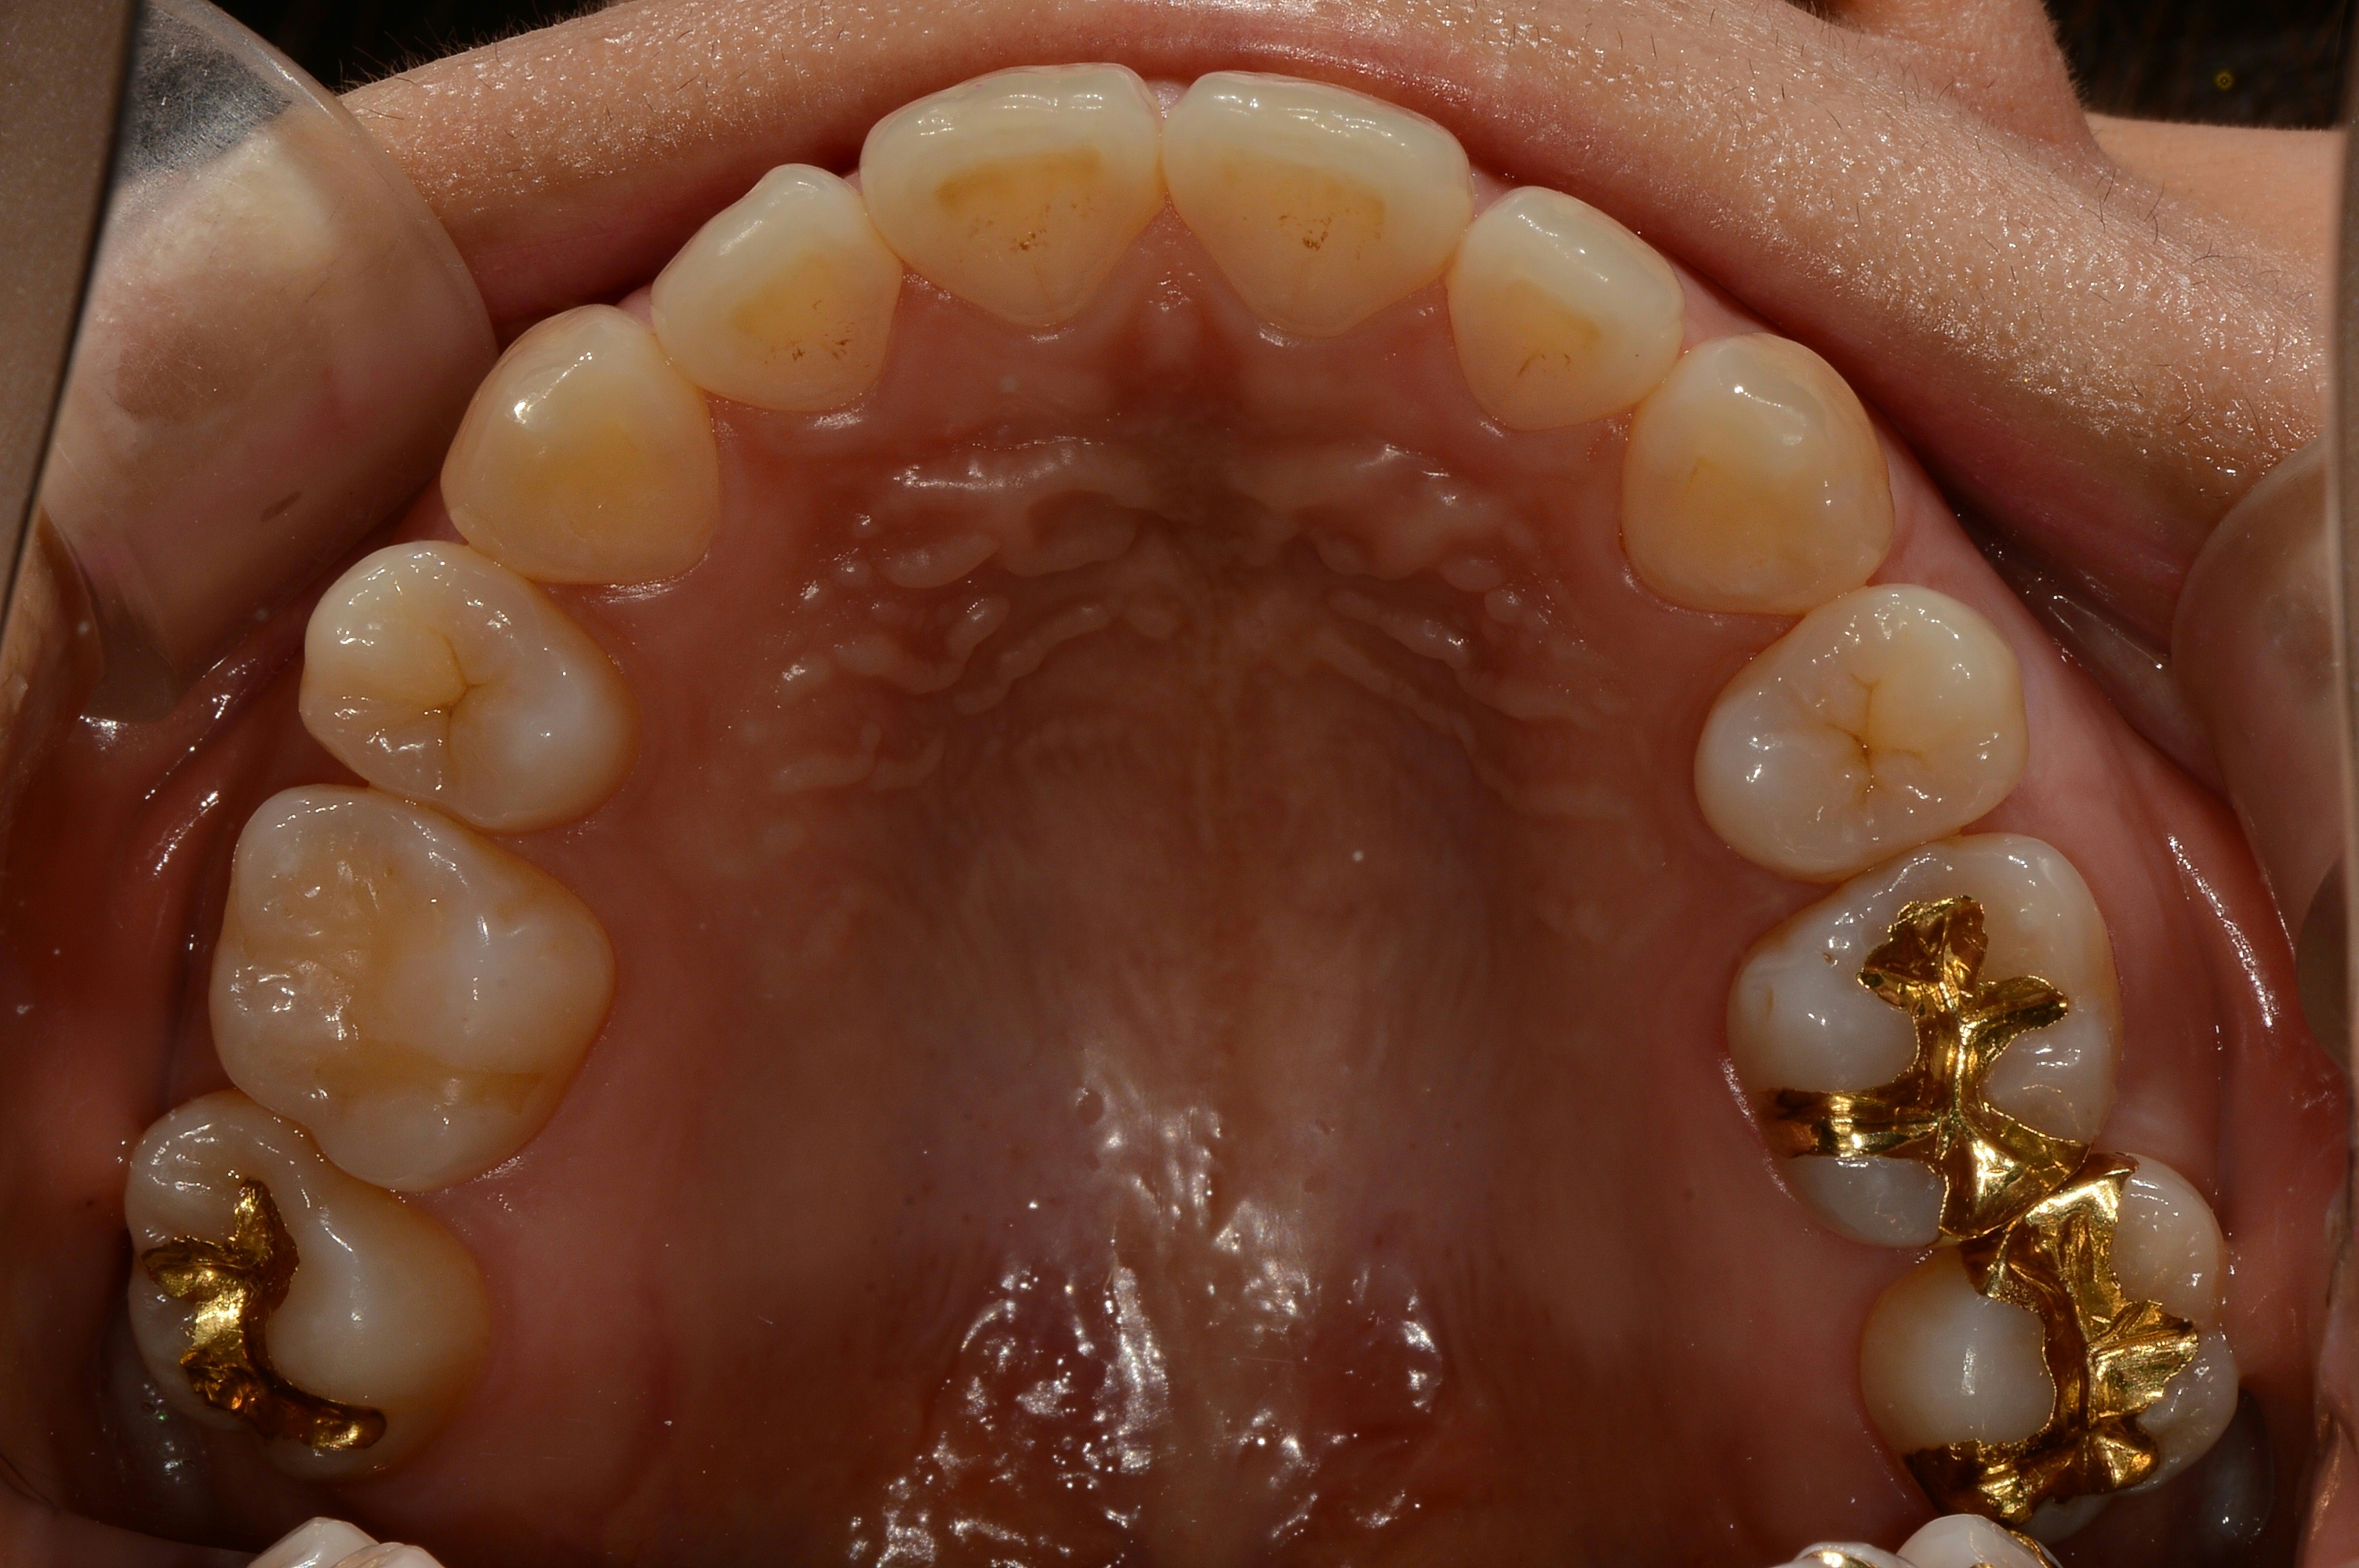

치료 후 사진입니다.